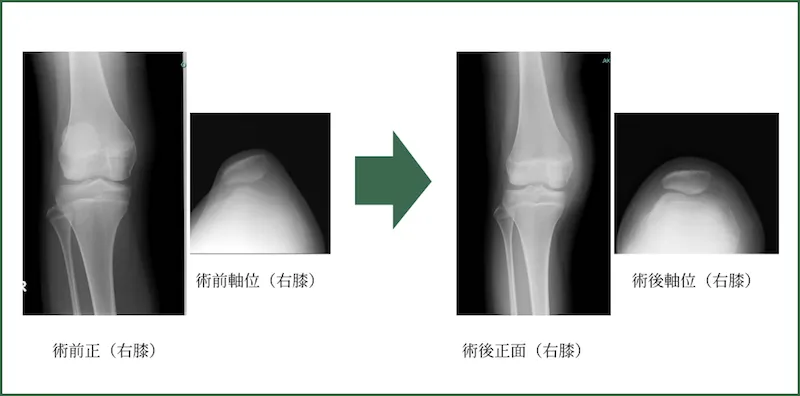

内側膝蓋大腿靭帯再建術

(MPFLR: Medial patellofemoral ligament reconstruction)

反復性膝蓋骨(膝のお皿)脱臼に行う手術方法です。膝屈筋腱を移植腱とします。解剖学的再建を行います。ただし、アライメントがかなり悪い場合は骨を移動させる方法もあります。

脱臼パターンも様々です。例えば伸展時に脱臼するパターン、屈曲時に脱臼するパターンです。それにより、いくつかある外側のリリース方法(極度の引っ張りを解除する)を選択します。

手術時間:平均80分

出血量:20ml程度

年間件数:数例程度 (2020年)